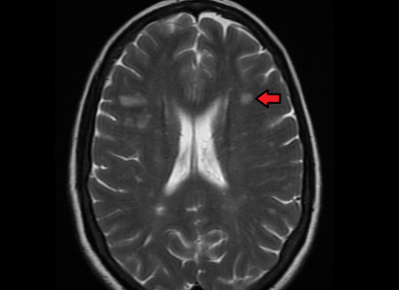

研究人员使用一种名为 SuStaIn 的人工智能工具来查看 6,322 名 MS 患者的 MRI 脑部扫描结果。SuStaIn 在无人监督的情况下工作,并在一段时间内设法在这些脑部扫描中识别出三种以前未知的模式。科学家根据 MRI 扫描中最早出现的异常将它们命名为 MS 的三种亚型——皮质主导、外观正常的白质主导和病变主导。科学家在另一轮 SuStaIn 研究中证实了这些发现,该研究分析了一个由 3,068 名患者组成的独立独立队列。AI 系统能够根据新定义的 MS 亚型对它们进行分类。